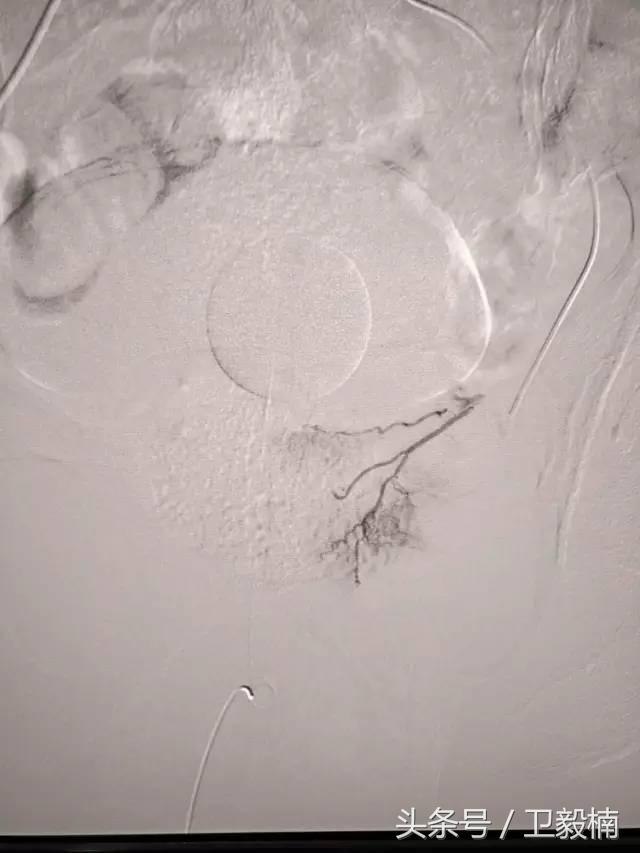

(1)选择性肿瘤供血动脉灌注化疗+栓塞治疗恶性肿瘤。

(3)应用栓塞术治疗海绵状血管瘤,蔓状血管瘤,子宫肌瘤,骨肉瘤,鼻咽部纤维血管瘤等。